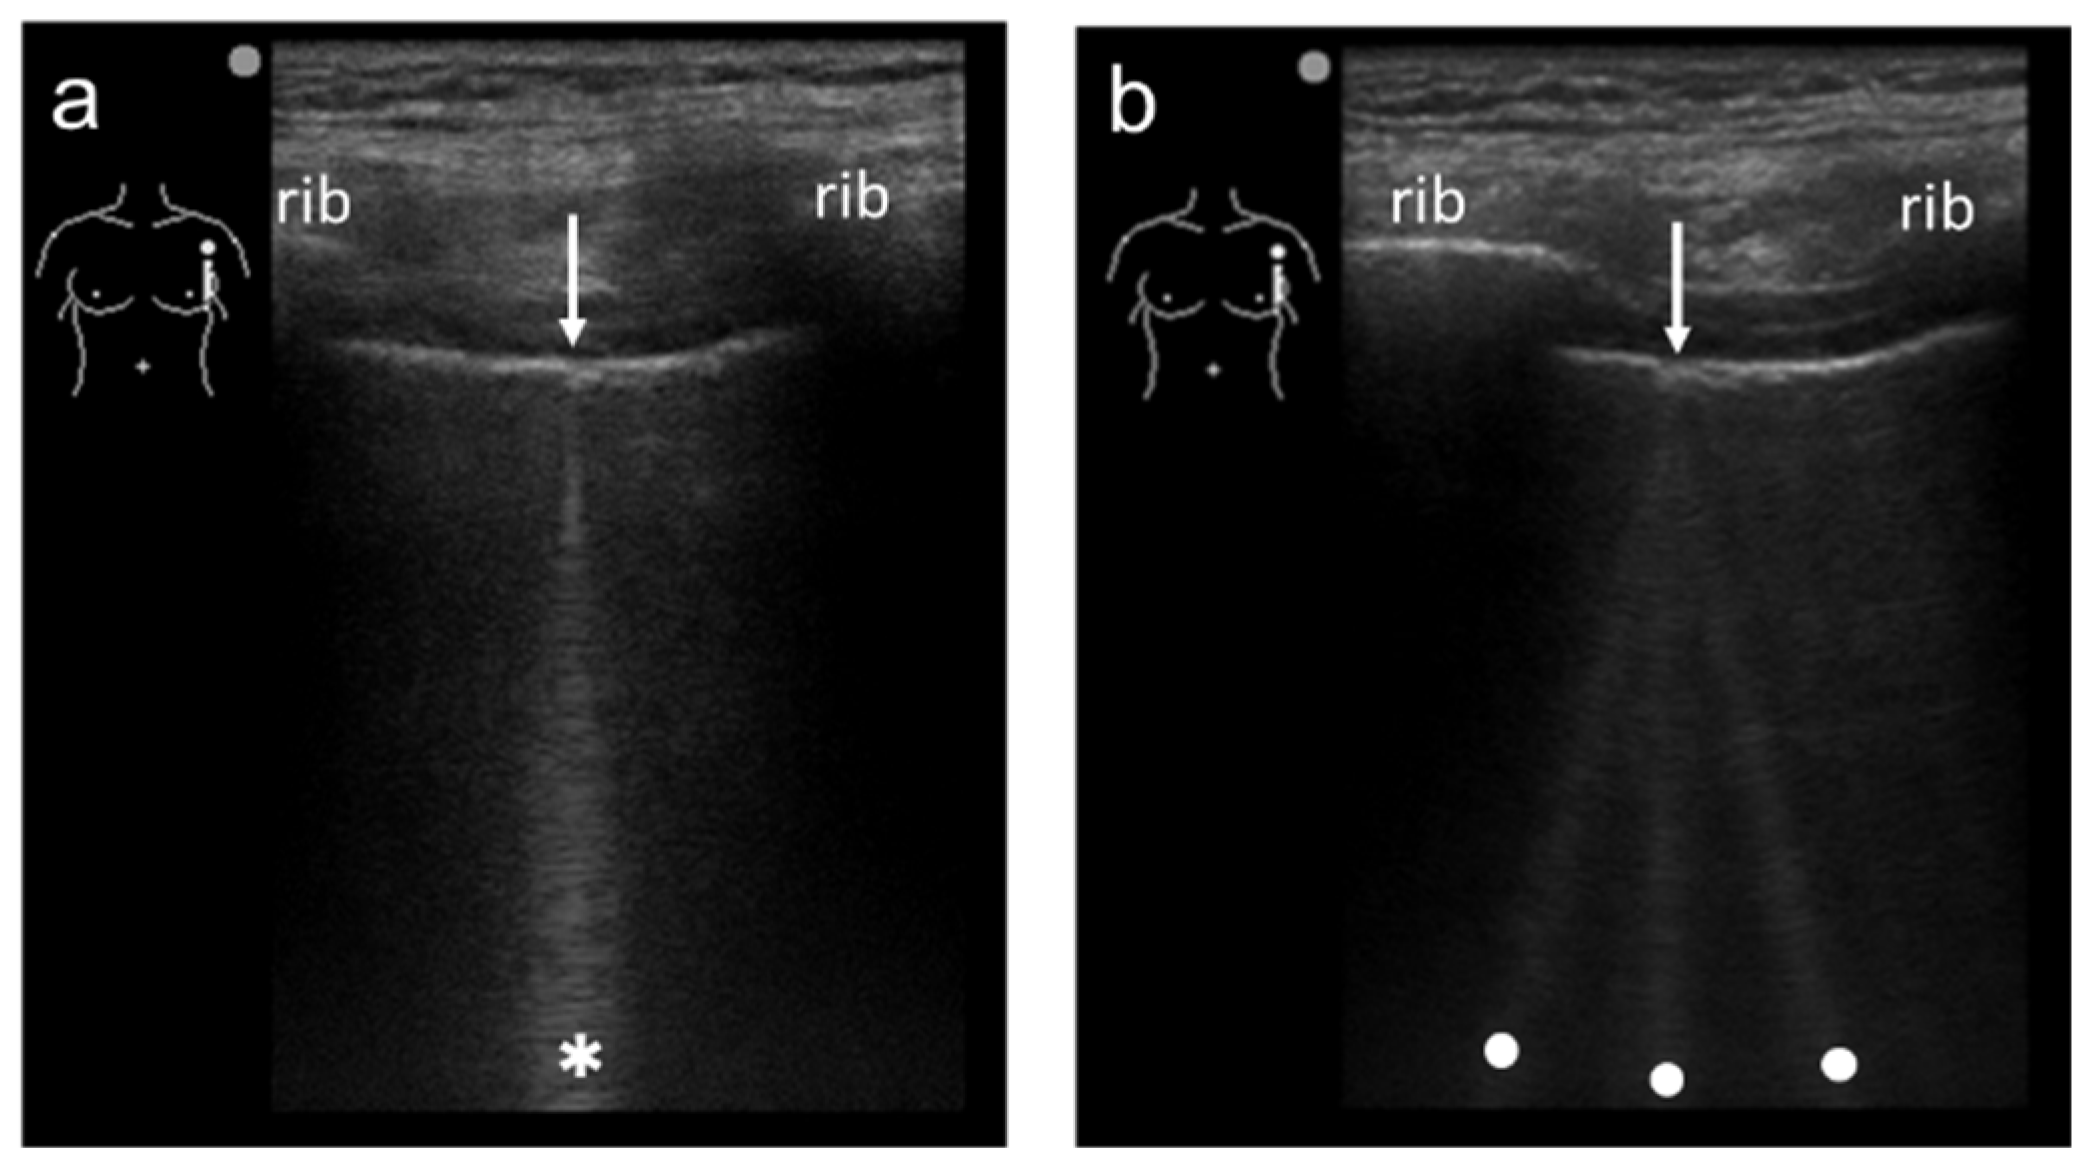

2.2. The Theory of Acoustic Trap

2.3. Our Basic Research Supporting the Theory